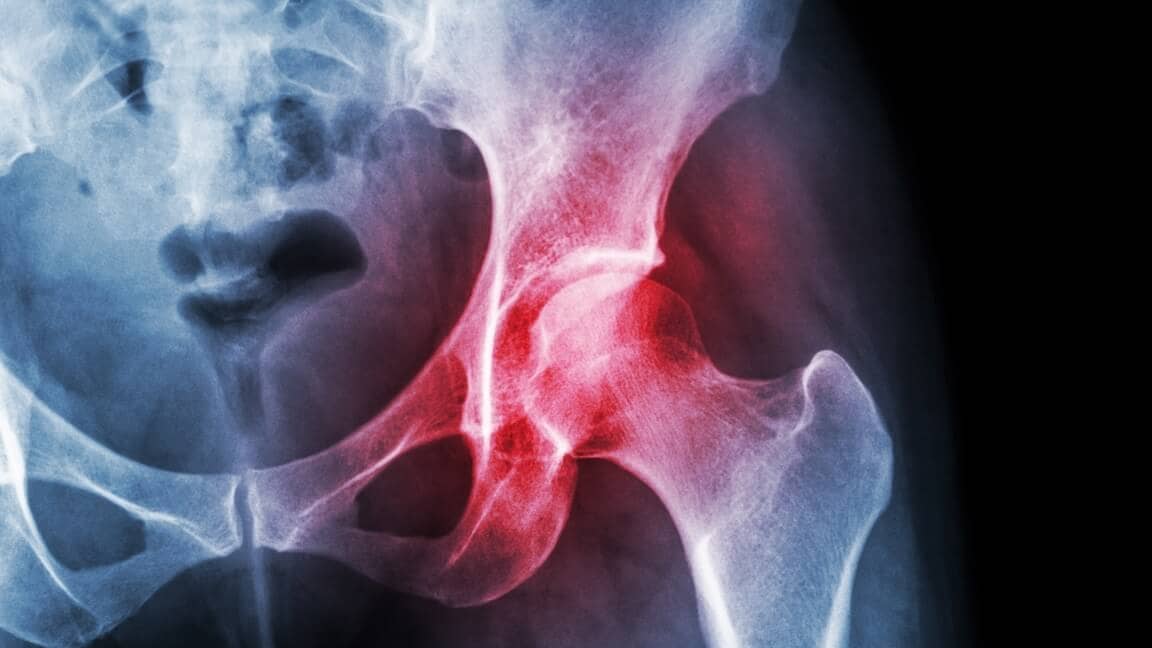

Osteoporóza (riedke kosti) je stav, ktorý postihuje kosti. Jeho názov pochádza z latinčiny pre „porézne kosti“.

Vnútro zdravej kosti má malé priestory. Osteoporóza zväčšuje veľkosť týchto priestorov, čo spôsobuje, že kosť stráca pevnosť a hustotu. Okrem toho vonkajšia časť kosti slabne a stenčuje sa.

Ľudia s osteoporózou sú vystavení vysokému riziku zlomenín kostí pri vykonávaní bežných činností, ako je státie alebo chôdza. Najčastejšie postihnuté kosti sú rebrá, boky a kosti v zápästiach a chrbtici.